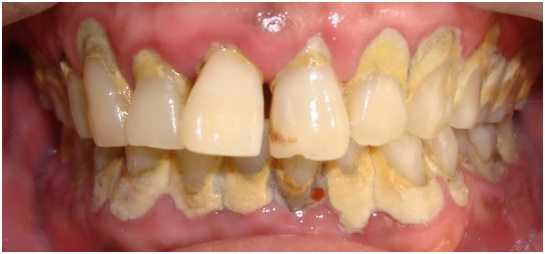

牙龈炎看起来挺严重呢,不,更严重的是牙周炎。除了上述牙龈炎症状外,当还有牙周袋大于3mm,牙齿邻面附着丧失大于1mm,牙齿X线片显示压槽骨有吸收,严重者甚至有口臭、溢脓、牙齿松动等,这些就可以确诊牙周炎了。看到下面这张图,是不是有一种“使我不得开心颜”的惆怅呢,还有下面的X牙片,让我想起了《千年泪》中“摇摇欲坠,不只你的泪”,这里摇摇欲坠的还有你的牙。